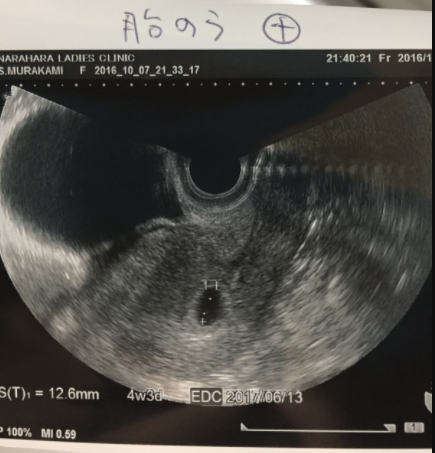

4週3日(4w3d・男の子)|さぁーや さん(32歳)

エコー写真撮影時のエピソード:

初めての赤ちゃんで、エコーを見に行くたびに旦那も一緒に行きました。その産院はUSBメモリーにエコーをすべて入れてくれて動画で残すことができました。

妊娠中期に性別がわかり、元気な男の子でした。いつも両手を顔の横で曲げて写っていて、産まれてからもよくそのポーズをしていたので、この子がお腹にいたんだなぁって実感が湧きました。